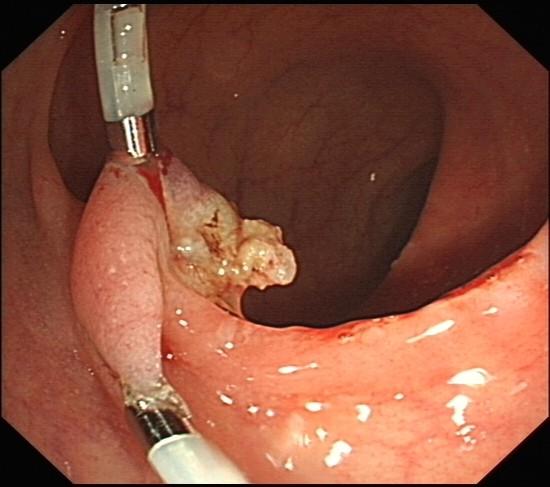

伪装成痔疮脱出的直肠息肉

直肠息肉

emr治疗难治性结直肠病变 可安全有效地治疗体积.

经肛门排出巨大结肠息肉1例论文

新生儿直肠息肉图片